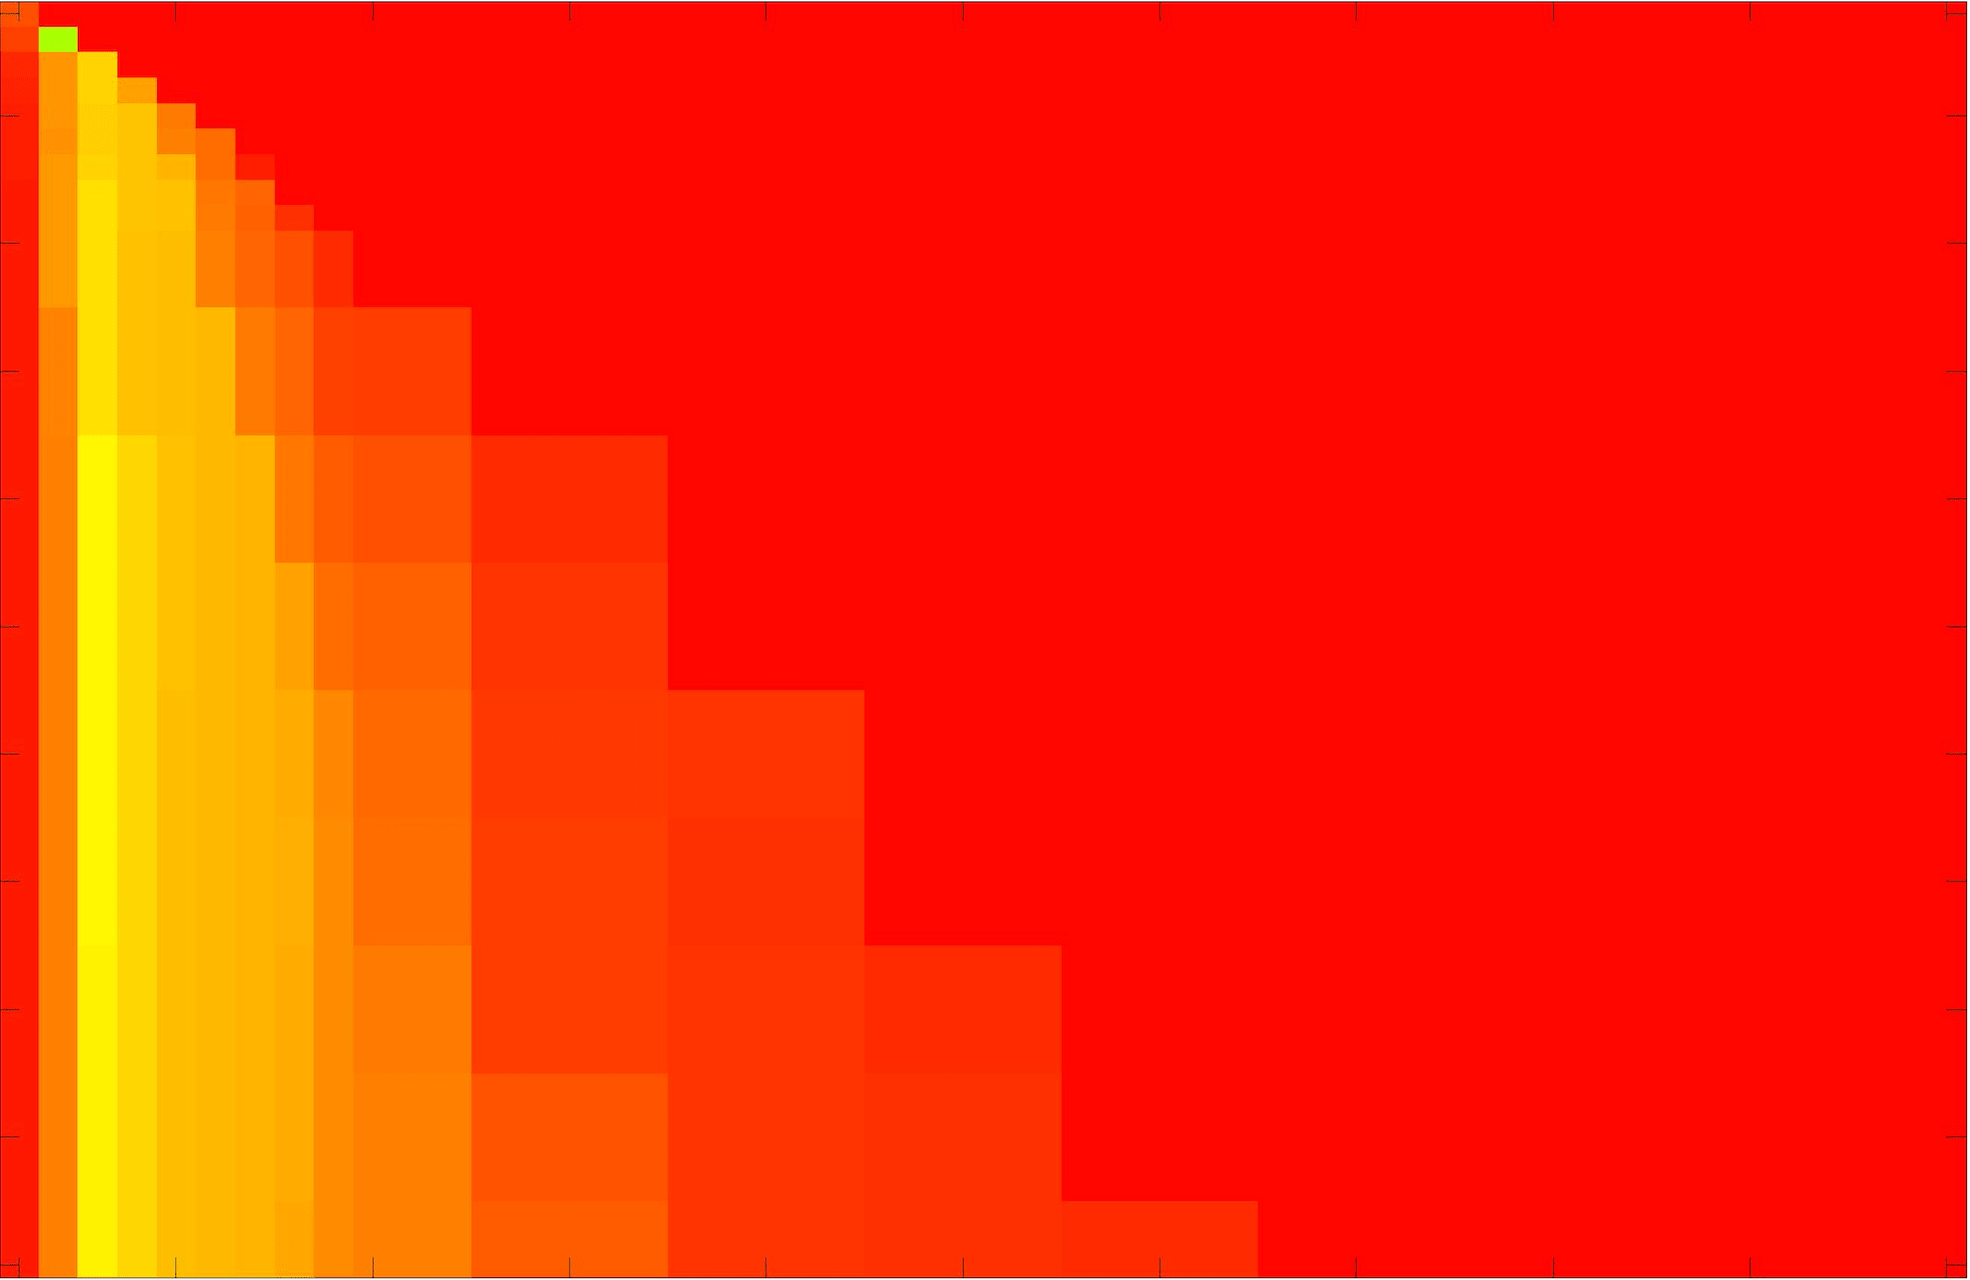

where refers to the number of points in the enclosed region. This takes values in the range , with higher TC values indicating a more accurate segmentation. In the following we will represent accuracy visually from red () to green (), with the intermediate scaling of colours used shown in Fig. 8. This will be particularly relevant in §7.2.

The TC values for the parameter sets are presented as heatmaps in Figs. 11–13. A heatmap is a convenient way to display accuracy results for hundreds of tests concisely. In Fig. 9 we give an example heatmap with the same axes used for those in Figs. 11–13. For each of the combinations of parameter values we give the TC value of the segmentation result and represent it by the appropriate colour. The corresponding colour scale is shown in Fig. 8. Qualitatively, the more green areas of the heatmap the more accurate the model is for a wider set of parameters. Example results for Test Image 5 when varying (with ) for the proposed model are given in Fig. 10. Here it can be seen what each accuracy result corresponds to visually.

Note. The axes have been removed from the heatmaps in Figs. 11–13 for presentational clarity. However, to be explicit, the axes used in all heatmaps are the same as those in Fig. 9.

Synthetic Images. These results are presented in Fig. 11. For Test Images 1–2 we see poor parameter robustness from all competing models, except for GAV which performs reasonably well. However, the proposed model has minimal parameter sensitivity for these images, with good results achieved for almost every combination of values tested. For Test Image 3 all models have a reasonable parameter range (except for RSF), however the proposed model gives better quality results for a wider parameter range. The other models achieve reasonable results here as the foreground intensity of the ground truth is greater than the background , whereas for Test Images 1–2 they are equal . These results highlight the key advantage of the proposed model.

Real Images. In Fig 12 we present results for Test Images 4–6. Here, the proposed model performs in a similar way to its competitors because these images are more typical selective segmentation problems in the sense that there is a clear distinction between the foreground and background intensities. In particular, the values in each case are: Test Image 4 , Test Image 5 , and Test Image 6 . It can be seen that the proposed model is competitive compared to previous approaches. The performance is quite poor for Test Image 5, but is arguably still the best for this challenging case. In Fig. 13 we present results for Test Images 7–9. Here the proposed model outperforms previous approaches significantly for each image. This is mainly due to the type of image considered. Specifically, the true intensities are: Test Image 7 , Test Image 8 , and Test Image 9 . The proposed model is capable of achieving results where , with other models failing completely in these cases.